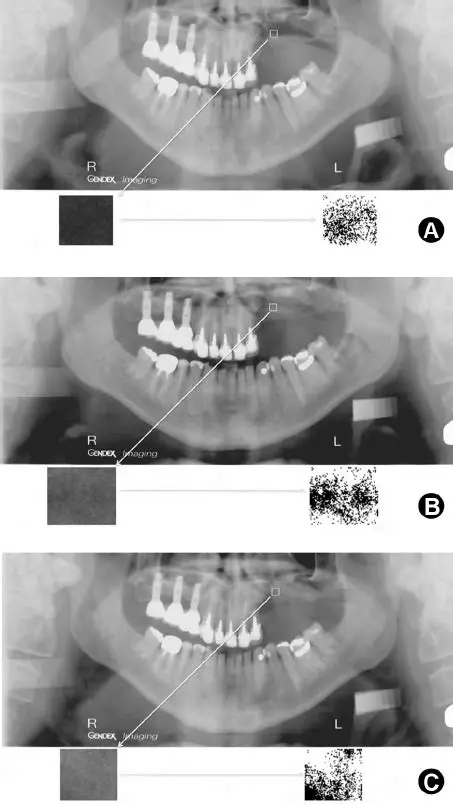

Panoramic radiographic examination